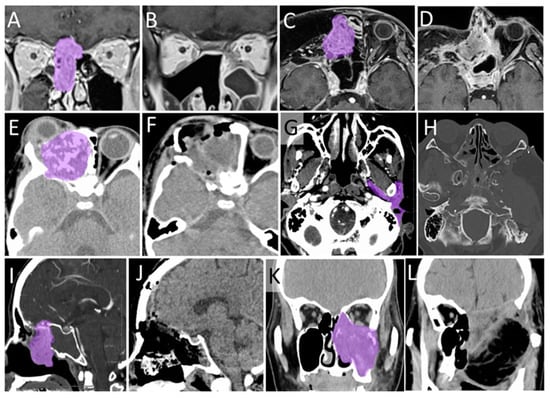

3.7. The Other Cases